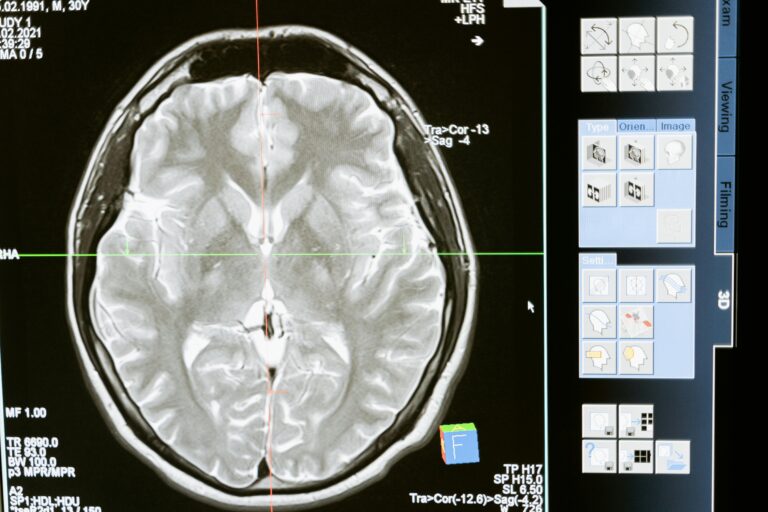

brain deformation